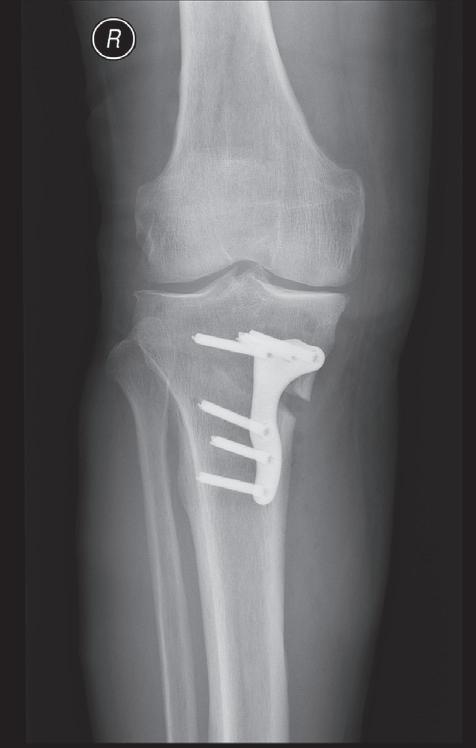

Obr. 19.6: Osteotomie valgizační – otevřená. Provádí se osteotomií z mediální strany proximální tibie a s následným rozevřením fragmentů do tvaru klínu, který koriguje deformitu s následnou fixací osteosyntézou. Předoperační (a) a pooperační rentgenový snímek (b)

Osteotomie má za cíl korekci kloubní osy se změnou zátěžových oblastí kloubu. Operace obnoví osu končetiny a odlehčí tlak na poškozenou oblast kloubu a zmírní tak subjektivní obtíže nemocného. Příznivý výsledek obvykle přetrvává několik let. Dle poruchy osy rozlišujeme osteomie valgizační (korekce genu varum) a varizační (korekce genu valgum). V praxi se provádí klínovitá osteotomie s vytětím kostního klínu, sesazením obou fragmentů a fixací osteosyntézou (tzv. closed wedge osteotomie, obr. 19.5). Druhou možností je provedení jednoduché osteotomie s rozevřením obou fragmentů v klínovitém tvaru a fixace osteosyntézou (tzv. open wedge osteotomie, obr. 19.6). Dále podle anatomické lokality osteotomie rozlišujeme osteotomie distálního femuru (obr. 19.7) nebo proximální tibie. Artrodéza (ztužení kloubu) se primárně používá ve výjimečných případech (obr. 19.8). Je však možným řešením zejména po selhání aloplastiky, pokud není možná implantace nové náhrady. Vzhledem k faktu, že ztužení kloubu probíhá obvykle v terénu rozsáhlých kostních ztrát, používá se v poslední době ztužení kloubu pomocí implantátů – tzv. fúze kolenního kloubu (obr. 19.9). Nejde tedy v pravém slova smyslu o klasickou artrodézu – tedy kompletní primární kostní srůst femuru a tibie.